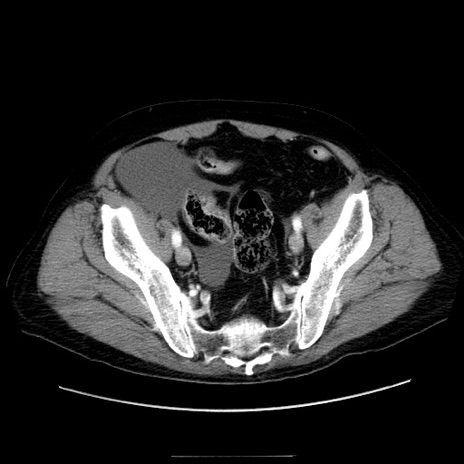

症例30(横断像)

【症例】80歳代男性

【主訴】臍周囲痛

【現病歴】約6時間前から臍下部痛が出現。次第に腹部膨隆・背部痛も生じてきたため来院。背部痛の場所は変化しない。

【身体所見】意識清明、BT 36.3℃、BP  131/87mmHg、P 87bpm、SpO2 100%(RA)、臍周囲自発痛・圧痛あり、反跳痛なし、自発痛部位に一致して板状硬あり、腹部膨隆、腸雑音減弱、CVA tenderness両側陰性。

【データ】WBC 19600、CRP 0.33